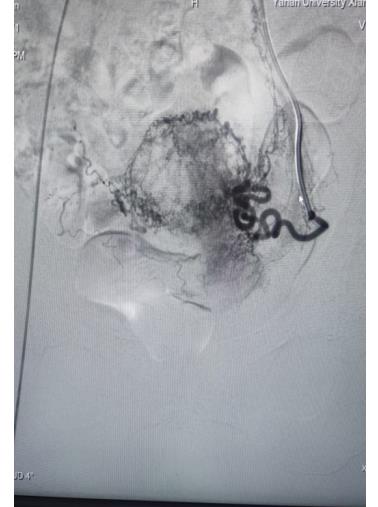

子宮動脈栓塞術屬于血管介入性治療,方法是于股動脈穿刺進針插入導管,在X射線造影下定位進入兩側子宮動脈,注入栓塞劑完全栓塞子宮動脈,從而達到止血或讓子宮肌瘤和病灶缺血壞死的目的;2022年12月6日,在崔旭輝主任、孟慶槐副主任醫(yī)師、馬力主治醫(yī)師等我院介入團隊協(xié)作下,成功為患者進行了雙側子宮動脈栓塞術,術后患者子宮異常出血停止,效果立竿見影,患者病情恢復良好。

右側子宮動脈栓塞前后對照